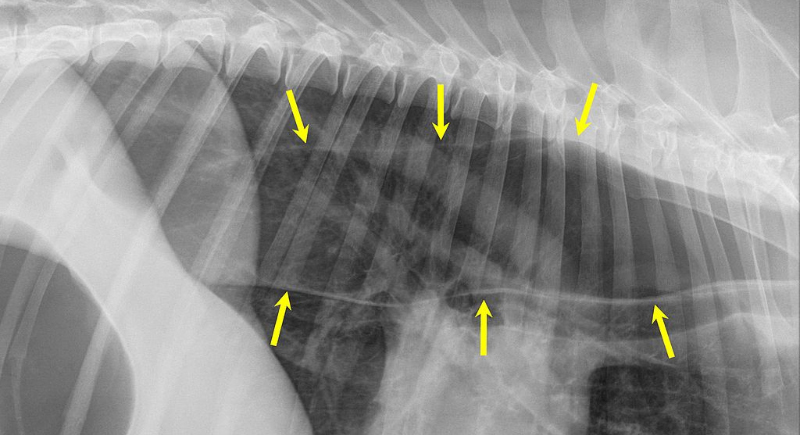

The esophagus works like a slide, carrying food from the mouth to the stomach. In dogs with megaesophagus, the slide loses its shape and strength. Food and water collect in the passage instead of moving smoothly downward, leading to regurgitation, weight loss, and constant hunger despite eating.